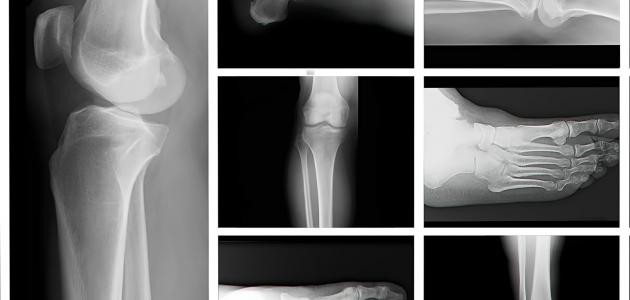

انواع الكسور